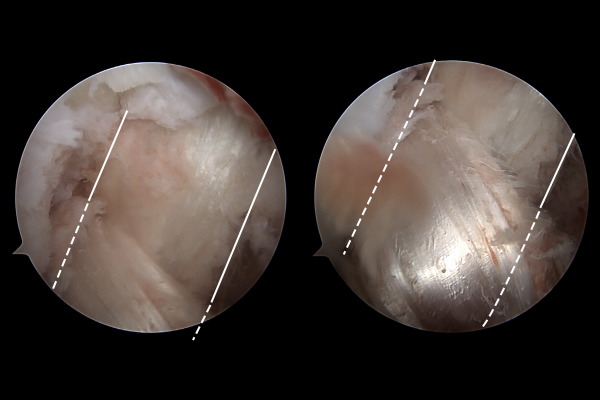

무릎의 뒤쪽에서 확인할 때의 내시경 사진입니다. 후방십자인대가 파열되어 보이지 않고 잔해만 남아있는 것이 확인됩니다.

뼛조각도 같이 떨어져 나온 것이 확인되어, 뼛조각을 제거해줍니다.